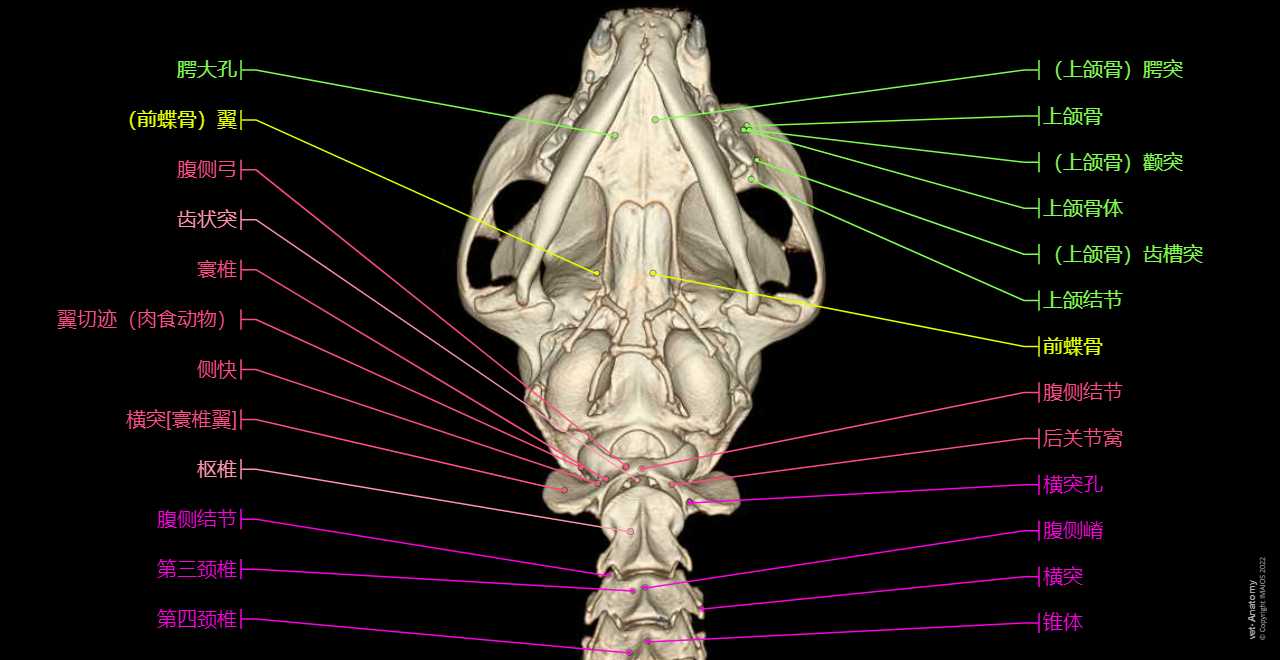

正常猫的头颈部CT解剖

- Antoine MICHEAU, MD , Denis HOA, MD , Susanne AEB Boroffka, PhD - dipl. ECVDI

- 发布日期: 2019年10月11日 | 最新更新 2025年3月18日